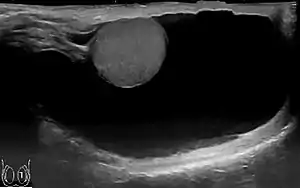

Primary hydroceles

The swelling is soft and non-tender, large in size on examination, and the testis cannot usually be felt. The presence of fluid is demonstrated by transillumination. These hydroceles can reach a huge size, containing large amount of fluid, as these are painless and are often ignored. They are otherwise asymptomatic, other than size and weight, causing inconvenience. However the long continued presence of large hydroceles causes atrophy of testis due to compression or by obstructing blood supply. In most cases, the hydrocele, when diagnosed early during complete physical examination, are small and the testis can easily be palpated within a lax hydrocele. However Ultrasound imaging is necessary to visualize the testis if the hydrocele sac is dense to reveal the primary abnormality. But these can become large in cases when left unattended. Hydroceles are usually painless, as are testicular tumors. A common method of diagnosing a hydrocele is by attempting to shine a strong light (transillumination) through the enlarged scrotum. A hydrocele will usually pass light, while a tumor will not (except in the case of a malignancy with reactive hydrocele).

The accuracy of the diagnosis must be ascertained. Great care must be taken to differentiate a hydrocele from a scrotal hernia or tumor of the testicle. Ultrasound imaging can be very useful in these cases. A hernia usually can be reduced, transmits a cough impulse, and is not translucent. A hydrocele cannot be reduced into the inguinal canal and gives no impulse on coughing unless a hernia is also present. In young children a hydrocele is often associated with a complete congenital type of hernial sac.